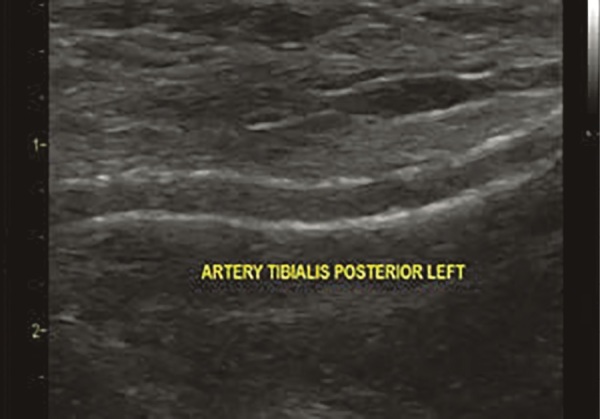

Abstract Image